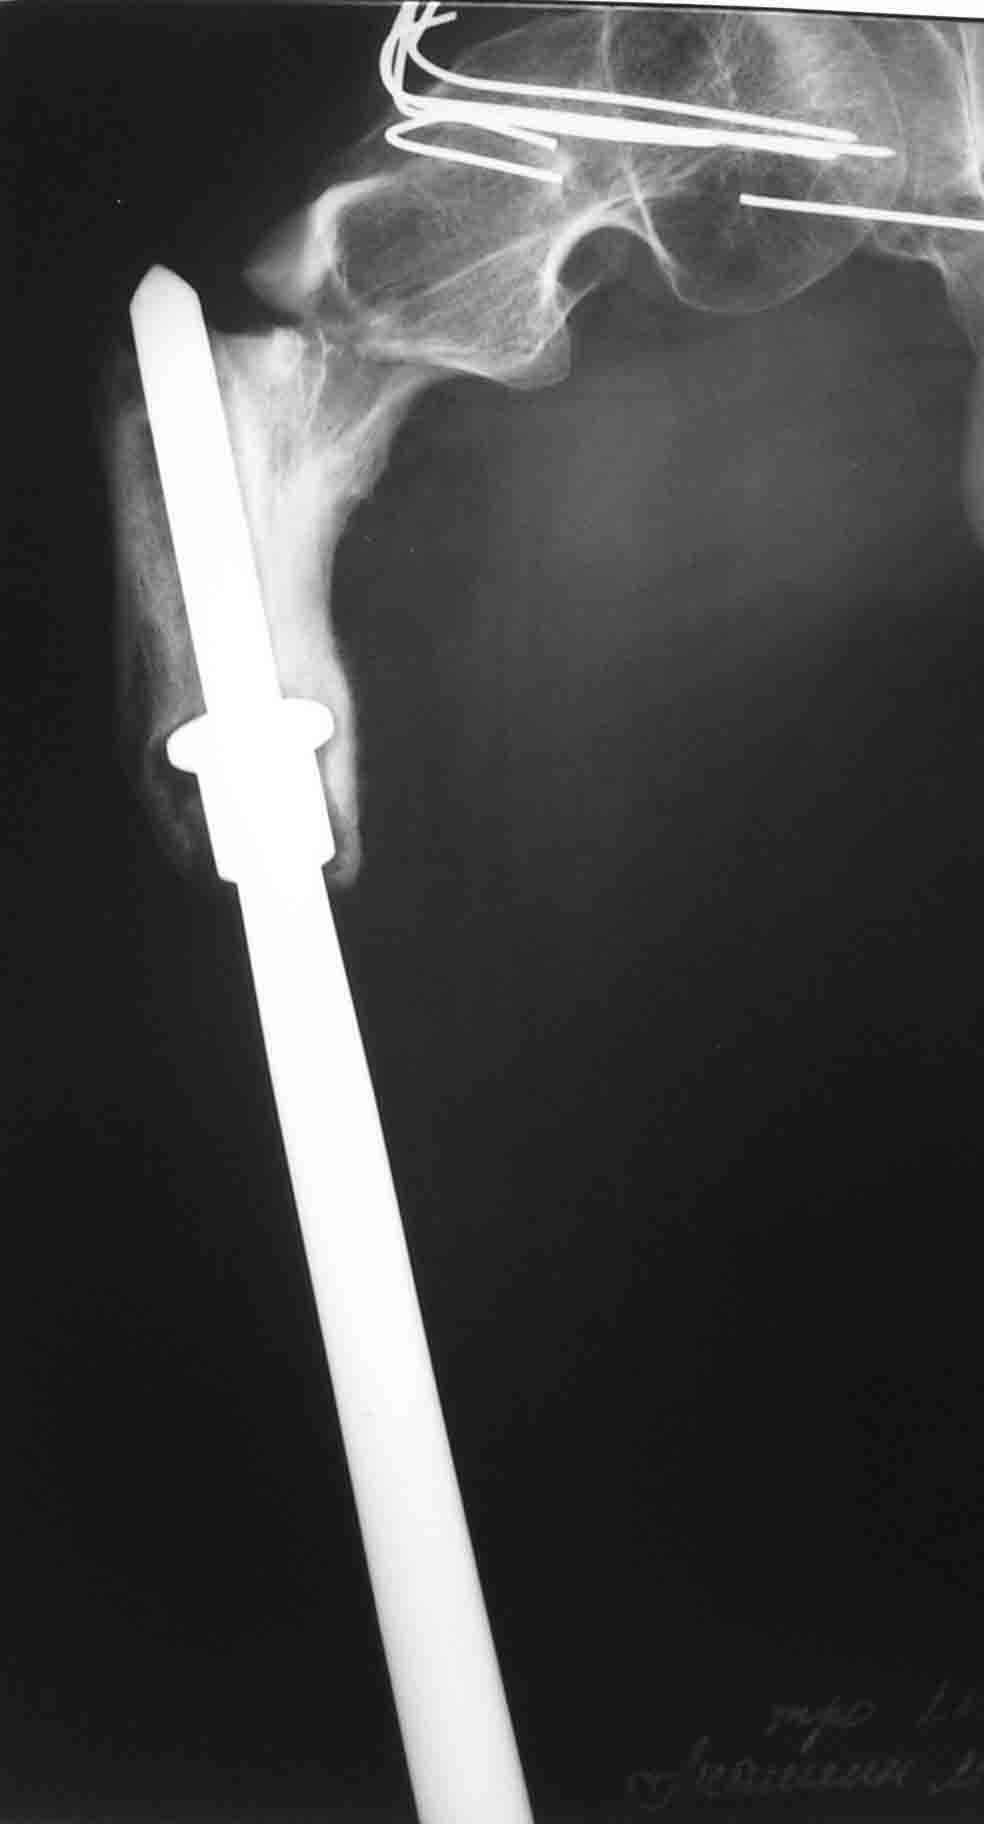

ГА> В марте этого года- повторный подвертельный перелом (см RG).

ГА> В настоящее время в коксите. Что дальше?

Пациент находится в Вологде. Это 500 км к северу от Москвы.

До травмы передвигался самостоятельно с дополнительной опорой (трость). Имеется укорочение ноги 15 см.

I would re-iterate suggestion for a fixed angle cable plate with cortical allograft struts around the prosthetic femur. Zimmer (and others) make them. The cables get purchase to the shaft by 1) go through horizontal slots in the plate or 2) onto grooves in the plate. The struts would be fixed by the cables too and keep the metal cables physically away from the metal prosthesis to minimize galvanic or fretting corrosion.

Impressive that he has functioned so long with a prosthetic femur shaft and knee joint. What is the etiology of the shortness? Acute at the time of resection or lack of growth or other?